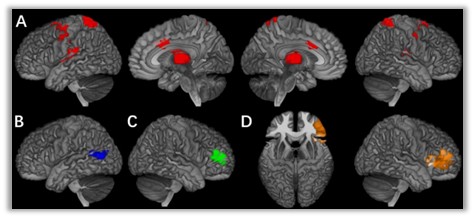

图一:多种精神疾病的认知脑指纹

A. 多动行为 (奖赏加工)B. 冲动行为 (控制加工) C. 注意缺陷 (控制加工) D. 品行障碍 (控制加工)

针对神经影像数据的高维共线性难题,研究团队开发了高维多变量分析方法,突破传统单模态研究范式的局限,系统性地从多个特异性认知环路分析了青少年精神和行为障碍的认知调控机制。研究定位了外向化障碍特征行为在不同认知领域中的特异性功能脑区,并进一步从神经影像层面对这些高度关联的特征行为进行分型,发现注意力缺陷障碍与品行障碍受到行为抑制任务下右侧下额叶区域的共同调控,从而揭示了两者共病的脑网络神经机制(Jia et al., Nat Hum Behav 2020)。

依托从青春期至青年期的大型纵向神经影像学队列(IMAGEN),研究团队识别出多种精神疾病共有的脑网络特征,并经由遗传学及临床数据双重验证,提出了“前额叶发育障碍导致执行功能受损”的共病理论(Xie et al., Nat Med 2023)。此外,为进一步阐明不同层级共病现象间的内在关联,团队深入解析了“神经共病因子”对内化及外化疾病脑网络的调控机制,首次提出了关于“精神疾病分层共病现象”的认知神经调控模型。